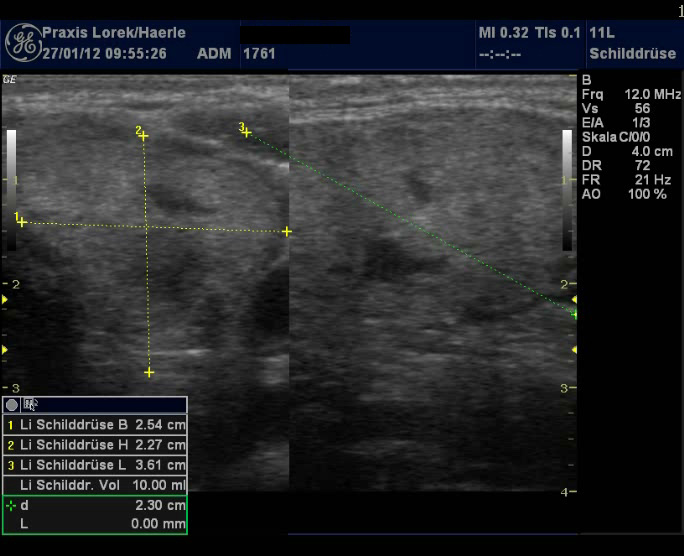

| Abb. 1 und 2:

Ungleichmäßige Echoarmut der Schilddrüse bei einer

31-jährigen Patientin, Schilddrüse mit etwa 8,8 ml etwas unterhalb

des Normbereichs, eher atrophische Verlaufsform (Ord-Thyreoiditis), Zufallsbefund

2008, es werden keine Symptome angegeben. Keine Knoten. |